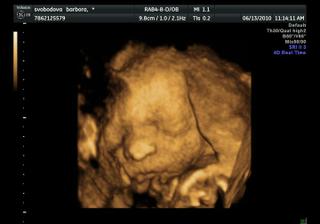

Náše bábetko a pupík🙂

Po 4 a půl letech jsme se rozhodli, že je nejvyšší čas pořídit si ten nejkrásnější dáreček 🙂 Po dvou snaženíčkách na nás vykoukly vytoužené //.